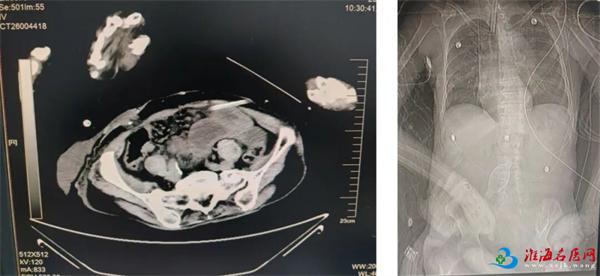

2026年1月10日凌晨,萧县黄口镇81岁的丁大爷(化名),因腹痛3天,在当地医院治疗效果不佳,呼叫120转入徐州一院,到急诊医学科时,患者出现意识模糊,血压骤降至60/30mmHg。腹部CT提示:腹盆腔肠管走行扭曲,多发肠管扩张、积气积液、部分可见气液平。初步诊断:肠梗阻、休克。

术前腹部CT

术前腹部CT非手术综合